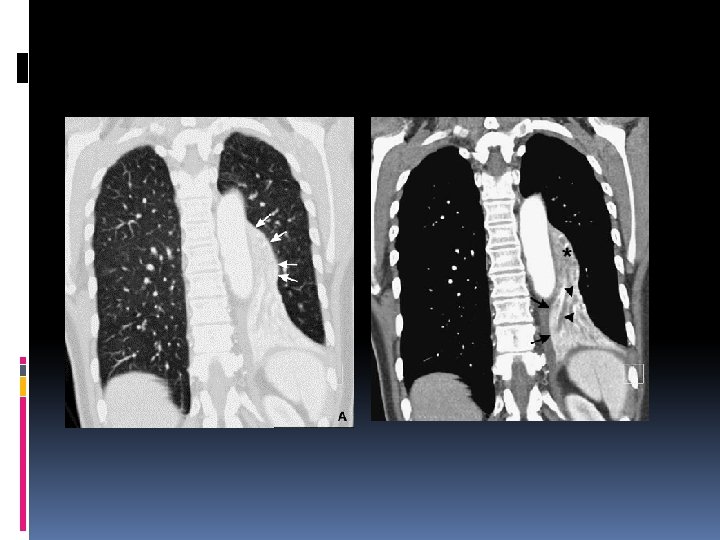

Signes directs L’opacité rétrocardiaque triangulaire à sommet hilaire et à base diaphragmatique sa limite externe scissurale est nette (aspect concave : flèches) effacement de la coupole les lignes paravértébrales lignes paraoesophagienne à droite paraaortique à gauche

Sur le profil : L’opacité se projette sur le rachis Effacement de la coupole homolatérale Sur la TDM : le lobe occupe la gouttière latérovertébrale limite antéroexterne : la grande scissure.

Lobe supérieur et lobe moyen droits se déplacent en avant en dedans En haut Comparable au collapsus du lobe supérieur droit. L’opacité est limitée en bas par la grande scissure

Lobe moyen et inférieur droits Le lobe inférieur comble la gouttière latérovertébrale et entraine avec lui le lobe moyen Efface le bord droit du cœur et la coupole diaphragmatique Limite externe oblique en bas et en dehors : sommation des deux scissures